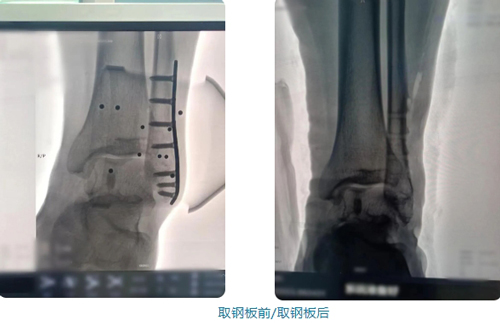

9厘米的钢板取出后,患者自我调侃“咋找不到创口?”手术机器人立了大功

健康大河南讯:(责编:方帅 鲁亚)手术是6月3日做的,院是6月7日出的,机器人辅助下取足踝部9cm的钢板,仅用了3个5mm的微口,术后第4天已经达到出院标准。

常规方法需要切开约与钢板一样长(9cm)的切口

机器人辅助下取钢板仅需3个5mm的微口

创口缩小了7.5cm

手术由韩颖干副主任亲自进行,借助天玑骨科手术机器人精准找到钢板及螺钉的位置后,通过3个5mm的切口,成功取出9cm的钢板。切口微小、恢复迅速,术后第4天就出院了。